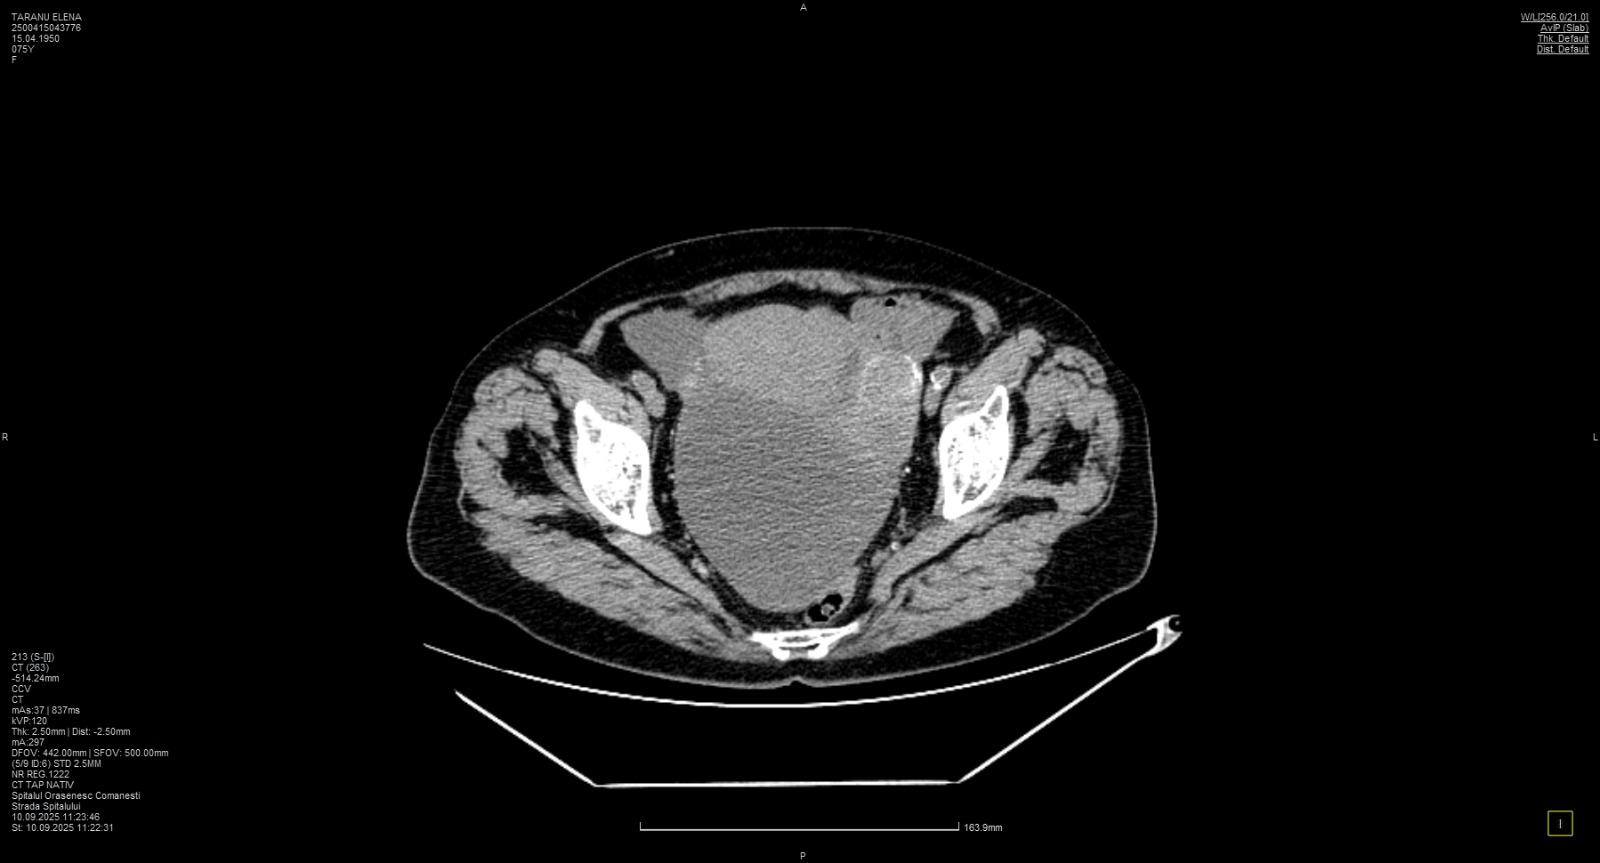

O pacientă de 74 de ani, diagnosticată cu tumoră pelviabdominală voluminoasă cu punct de plecare ovarian, a fost operată cu succes în cadrul unei intervenții chirurgicale de înaltă complexitate. Procedura a fost realizată printr-un abord multidisciplinar, sub coordonarea directorului medical, Dr. Chetrar Vadim, medic primar obstetrică-ginecologie.

Operația a presupus excizia completă a formațiunii tumorale, care afecta mai multe structuri din zona pelviabdominală și punea probleme majore de compresie asupra organelor interne. Dificultatea intervenției a constat atât în dimensiunea mare a tumorii, cât și în riscurile asociate vârstei înaintate a pacientei, necesitând o colaborare strânsă între specialități pentru a evita complicațiile intraoperatorii.